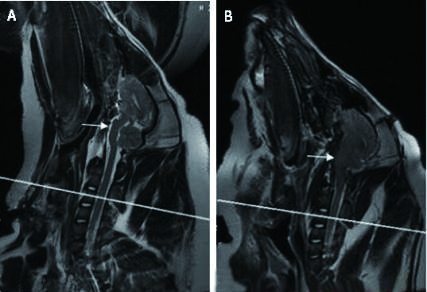

头颅MRI(T2WI)扫描后显示:血肿位于左侧脑实质内,左侧侧脑室受压变窄,中线向右侧偏移。造模前桥脑前池存在,为线条状高信号影;造模后桥脑前池消失,为线条状高信号影消失,提示脑组织移位,脑干受压(图 1)。

| C3水平(A):造模前脑池存在,为线条状高信号影;(B)造模后桥脑脑池消失,为线条状高信号影消失,提示脑组织移位,脑干受压(白色箭头示) 图 1 头颅MRI T2WI Fig 1 Head MRI T2WI |

|

脑疝的诊断证据往往依赖于临床症状和尸检[18]。与脑疝相关的临床典型的症状包括瞳孔大小和对光反射的改变,意识以及呼吸的改变等[18-19]。然而,支持脑疝的临床症状可能并不总是存在或难以与原发性脑干疾病相区分[20-21]。在硬膜下血肿患者和创伤性脑损伤的狗中,脑疝与较低的格拉斯哥昏迷量表(Glasgow Coma Scale, GCS)评分和较高的死亡率相关[22-23]。笔者应用广西巴马小型猪作为实验动物,建立了稳定的颅内高压致脑疝模型,并在既往的研究[6-7]基础上,提出急性颅内高压致脑疝标准(符合以下3条或以上即可诊断):(1)ICP≥50 mmHg;(2)呼吸频率明显减慢(RR≤6次/min)或出现潮式呼吸或暂停呼吸或呼吸停止;(3)心率≤50次/min,或≥200次/min和(或)伴心律失常;(4)单侧或双侧瞳孔散大至边缘;(5)头颅CT或MRI显示颅内血肿形成、中线偏移或桥脑前池消失。